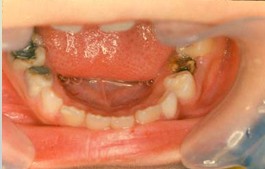

解析: 先天性无牙畸形 Total Anodontia

先天性无牙畸形的病因:外胚叶发育不全综合症、遗传性疾病。其临床表现:无汗、少汗、毛发稀疏、乳恒牙均可缺失、牙齿稀疏、牙形小、圆锥状。治疗:活动义齿修复。